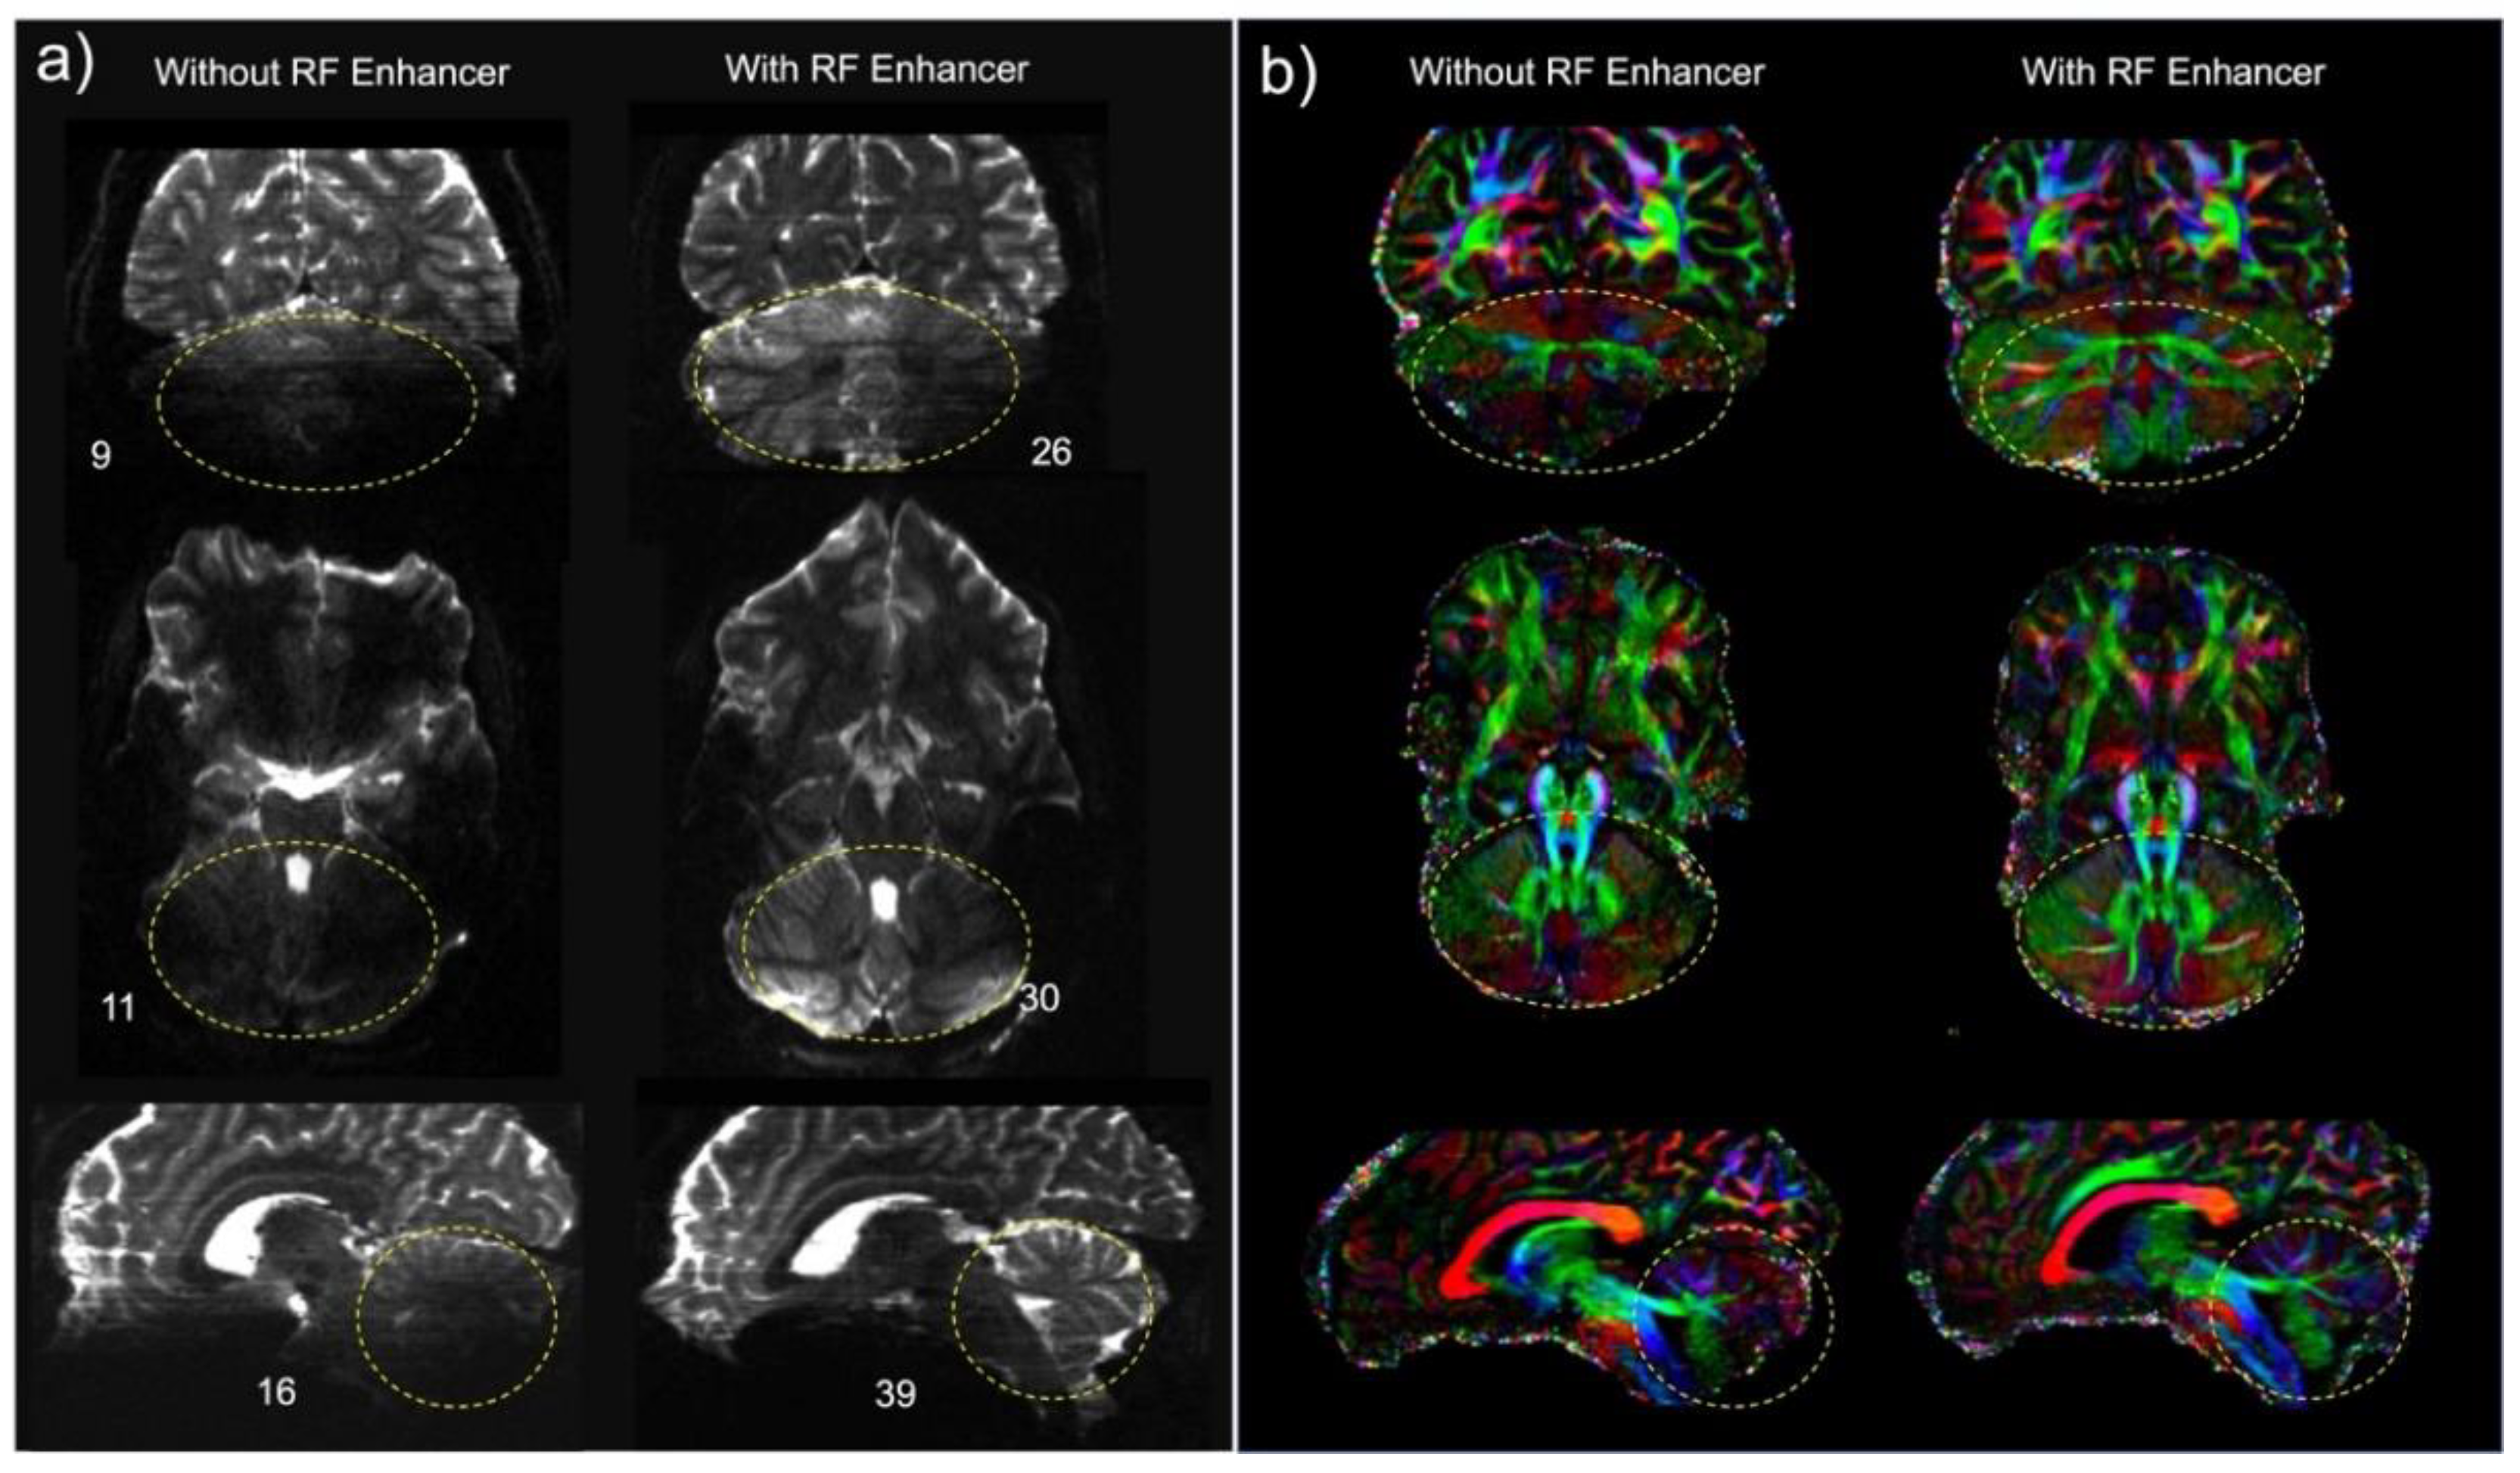

3. Results